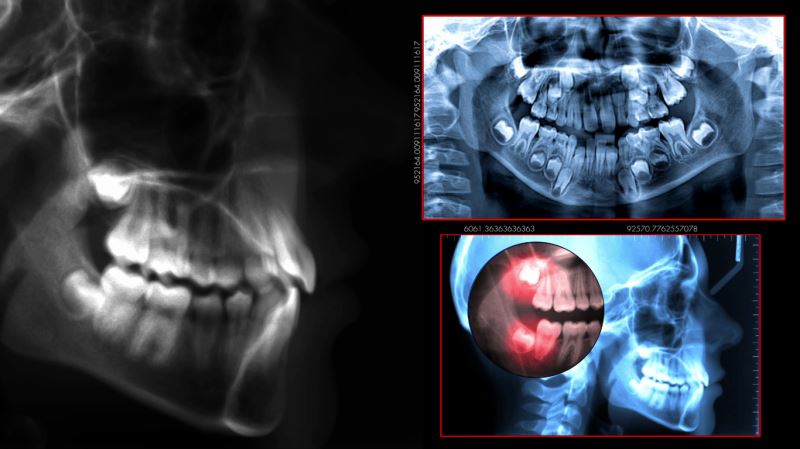

20 Yaş Dişinin Çekimi Sonrasında Dikkat Edilmesi Gereken Şeyler

48 - 72 saat sonra şiddetli ağrı oluşabilir. 24 saati geçen kanama, kötü bir tat ve koku hissi olursa derhal diş hekiminizi arayınız. ağız hijyeninizin iyi olmaması ve çok fazla sigara içilmesi alveolit "kuru boşluk iltihabı" denilen bu durumun oluşmasının en önemli sebeplerindendir.

dişler çene kemiğine gağlı olduğundan çekim sonrasında kemik ortaya çıkar ve siz çekilen dişten parça kaldıgını düşünebilirsiniz. o bölge ile hiç ilgilenmeyin. birkaç gün içerisinde açık kemiğn üzeri diş atiniz ile örtülecektir.

şayet diş çekimi normale göre zor olduysa; mutlaka çekilen diş bölgesine dışarıdan 8 saat boyunca saatte bir 5-10 dakika süreyle buz tatbiki yapmalısınız. şiş ve morarma buz tatbiki ile önlenmiş olacaktır.

cerrahi müdahale ile diş çekimi yapıldıysa; şişlik olabilir. bu normaldir.

gömülü diş çekimi veya apikal rezeksiyon yapılmış hastaların dikkat edeceği hususlar